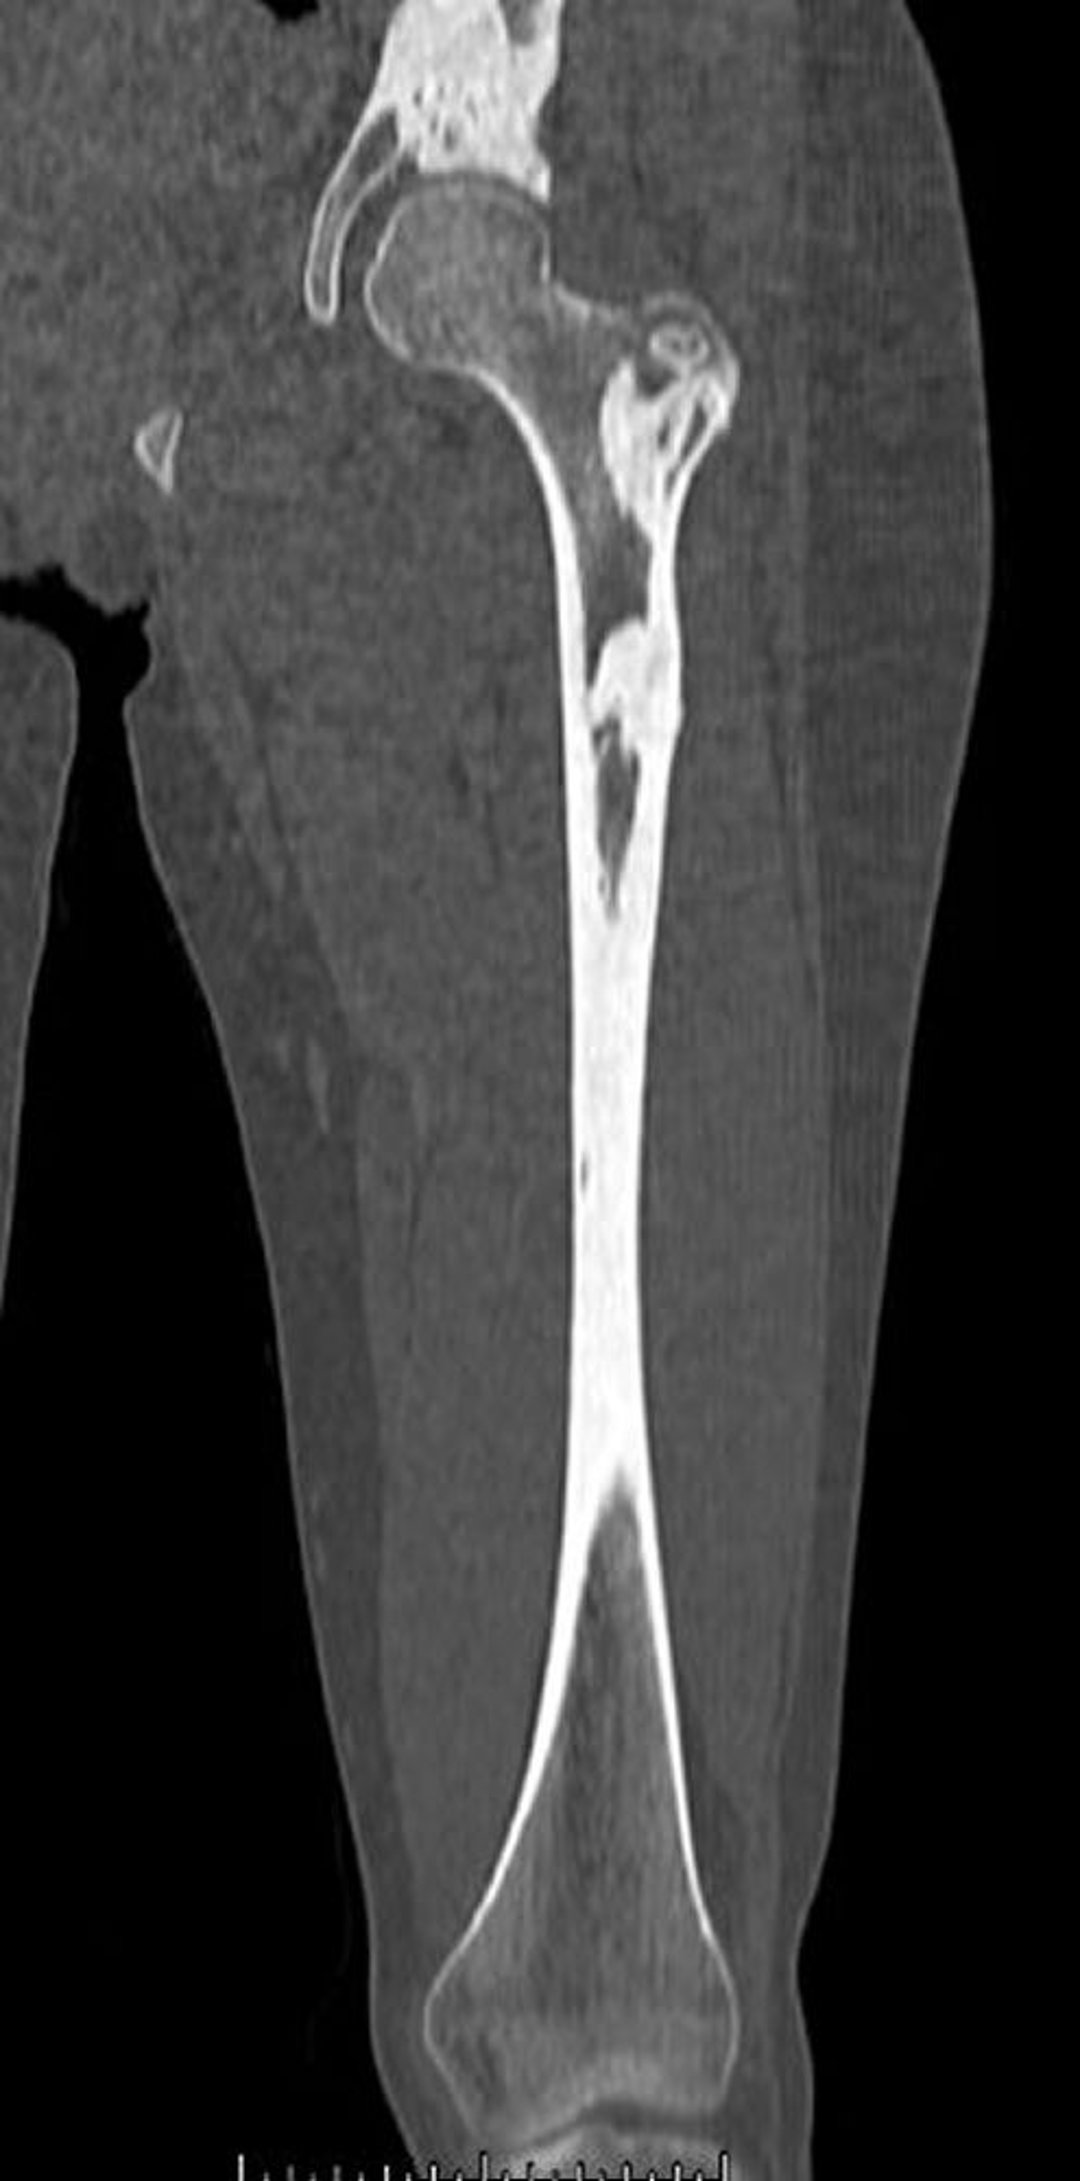

Мелореостоз (КТ-сканирование)

На этом КТ-скане показаны плотные костные поражения при мелореостозе бедренной кости и таза.

Image courtesy of Michael J. Joyce, MD, and David M. Joyce, MD.